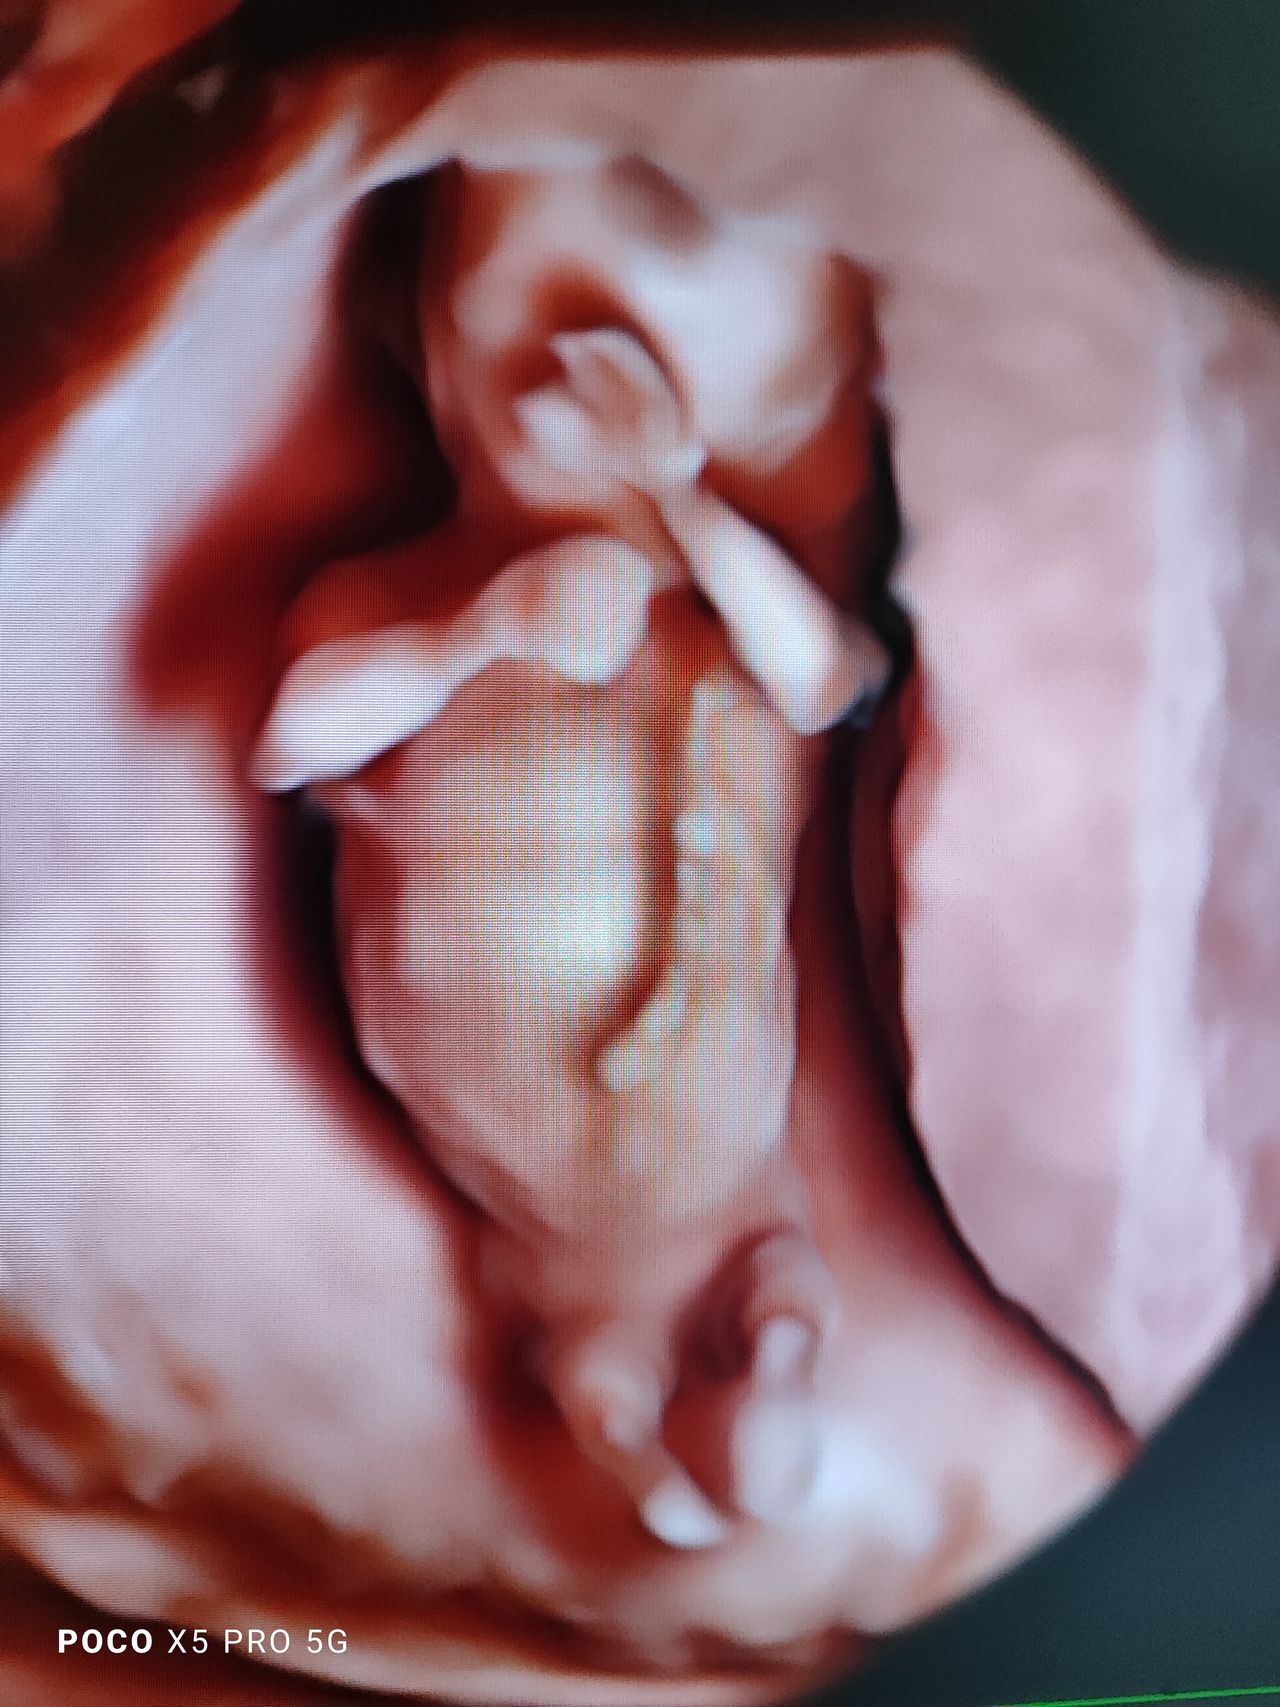

Dal 2015 al 2016 , frequenza presso U.O. Santa Maria delle Croci , Ravenna , periodo di Training di Chirurgia Laparoscopica, Endoscopica e di Isteroscopia ambulatoriale /office. In quell'anno nella stessa sede , ho  frequentato L'Ambulatorio di Diagnosi Prenatale acquisendo competenze in Ecografia Ostetrica del I-II-III trimestre.  Dopo la specializzazione ho proseguito la formazione e l'aggiornamento in particolare occupandomi dell’ Ecografia in ambito Ostetrico.

Ho acquisito "Certificate of Competence " da parte della Fetal Medicine Foundation per l'ecografia dell'11-13 settimana di gravidanza .

Da Maggio 2017 ad oggi faccio parte dello STAFF dell’Unità Operativa di Ostetricia e Ginecologia presso l’Ospedale "degli Infermi" di Faenza e dell’Ospedale "Morgagni Pierantoni "di Forli e mi occupo principalmente di Ostetricia , Gravidanza a Rischio, e dell'Ambulatorio Diagnosi Prenatale dove eseguo ecografie genetiche del I trimestre ed ecografie morfologiche e del III trimestre di gravidanza .